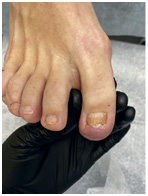

Иллюстрация к книге — Подология понятно. Важен каждый шаг. Справочник по проблемам подологии для клиентов и мастеров эстетики [i_269.jpg]

Иллюстрация к книге — Подология понятно. Важен каждый шаг. Справочник по проблемам подологии для клиентов и мастеров эстетики [i_270.jpg]

Иллюстрация к книге — Подология понятно. Важен каждый шаг. Справочник по проблемам подологии для клиентов и мастеров эстетики [i_271.jpg]

Иллюстрация к книге — Подология понятно. Важен каждый шаг. Справочник по проблемам подологии для клиентов и мастеров эстетики [i_272.jpg]

Результат работы за 5 месяцев: подолог использовал крючковые коррекционные системы, а хирург сделал пластику внутреннего бокового валика (из-за хронических воспалений боковой валик стал гипертрофированным и давил на ноготь, от чего клиент испытывал постоянный дискомфорт)